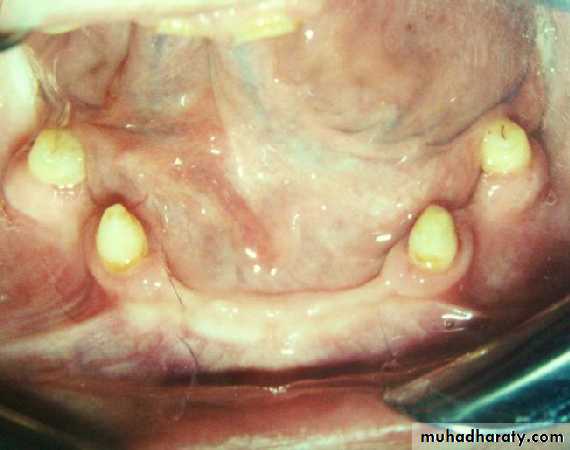

• 1) Bilateral distribution (avoid unilateral and diagonal).

2) Natural teeth orimplants as antagonists.

• 3) Endodontic treatment

• possible.• 4) min. 5mm periodontal

• attachment• min. 3mm attached gingiva.

• min. 2-3mm abutment height.

• no bony undercuts interfere

• with the insertion.

• 5) sufficient space between the abutment

• and the opposing.• 1) Long (6-8mm):